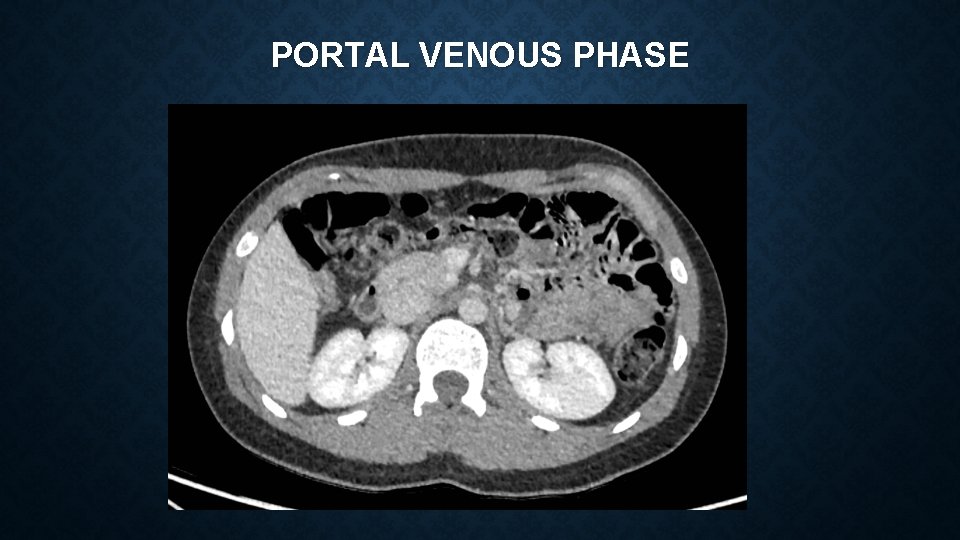

PORTAL VENOUS PHASE

MEDIAN ARCUATE LIGAMENT SYNDROME Vague constellation of symptoms which can include : • epigastric pain, postprandial pain, chronic non-specific abdominal pain, nausea, vomiting, weight loss Often a diagnosis of exclusion – reliant on clinical features and imaging findings Investigations include – CT angiogram and duplex ultrasonography CT – focal narrowing of coeliac artery with post-stenotic dilatation USS – Peak systolic velocities of >200 cm/s are suggestive of MALS